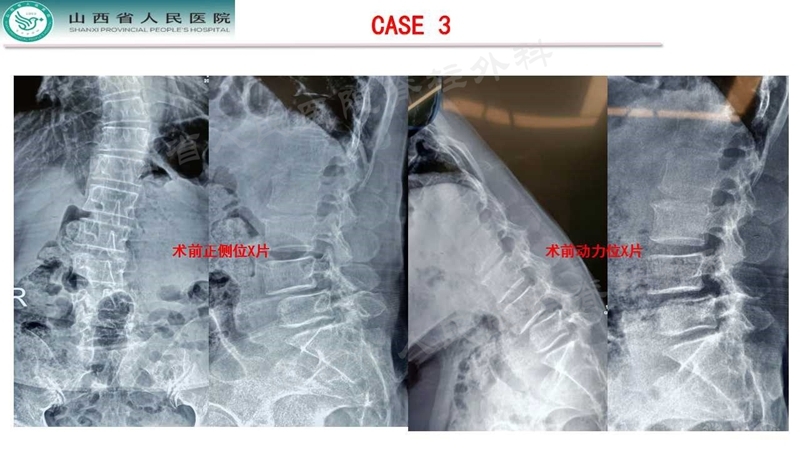

Case 3